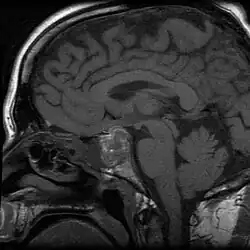

Apoplexy (from Ancient Greek ἀποπληξία (apoplexia) 'a striking away') refers to the rupture of an internal organ and the associated symptoms. Informally or metaphorically, the term apoplexy is associated with being furious, especially as "apoplectic". Historically, it described what is now known as a hemorrhagic stroke, typically involving a ruptured blood vessel in the brain; modern medicine typically specifies the anatomical location of the bleeding, such as cerebral apoplexy, ovarian apoplexy, or pituitary apoplexy.[1][2][3]

From the late 14th to the late 19th century, the diagnosis apoplexy referred to any sudden death that began with abrupt loss of consciousness, especially when the victim died within seconds after losing consciousness. The word apoplexy was sometimes used to refer to the symptom of sudden loss of consciousness immediately preceding death. Strokes, ruptured aortic aneurysms, and even heart attacks were referred to as apoplexy in the past, because before the advent of biomedical science, the ability to differentiate abnormal conditions and diseased states was limited. Although physiology, as a medical field, dates back at least to the time of Hippocrates, until the late 19th century, physicians often had inadequate or inaccurate understandings of many of the human body's normal functions and abnormal presentations. Hence, identifying a specific cause of a symptom or of death often proved difficult or impossible.[4][5][6][7][8]

To specify the site of bleeding, the term "apoplexy" is often accompanied by a descriptive adjective. For instance, bleeding within the pituitary gland is termed "pituitary apoplexy", and bleeding within the adrenal glands is referred to as "adrenal apoplexy".[9]

Apoplexy also includes hemorrhaging within the gland and accompanying neurological problems, such as confusion, headache, and impairment of consciousness.[10]